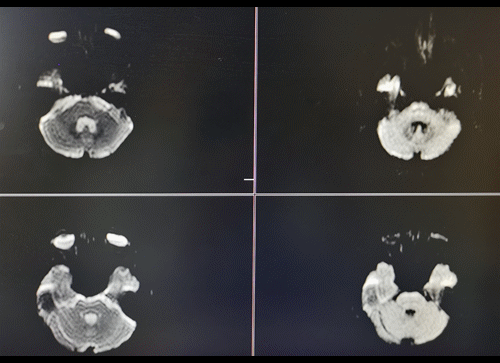

图1 MRI未见明显新发病灶。

图2 头颅CTA提示右颈内海绵窦段动脉瘤,基底动脉中段重度狭窄。

右颈内动脉海绵窦段起始部类圆形瘤样扩张,最大约19mm╳14mm,瘤颈约14mm,基底动脉中段重度狭窄。